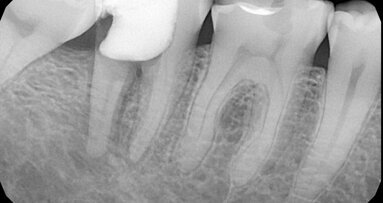

Dijagnoza preosetljivosti korena zuba zahteva detaljnu anamnezu, metodološki pregled i radiografiju.

Kao moguće uzroke preosetljivosti stomatolog mora prvo da odbaci pojave kao što su zubni karijes, patološke promene pulpe, vertikalna naprsnuća, pukotine na vrhu zuba, abfrakcije, protetske nadoknade koje nisu idealno postavljene ili zub u hiperfunkciji.